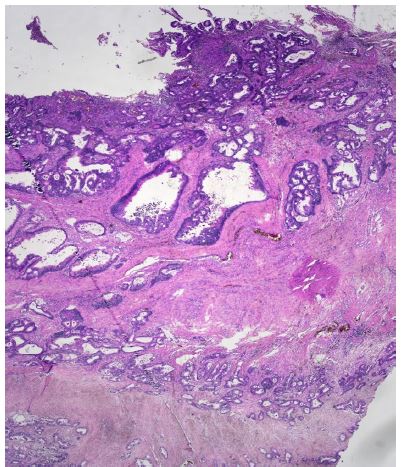

An abdominal Computed Tomography (CT) scan discovered a dilated colon up to the splenic flexure. A CT scan did not show regional nor distant metastases. Subsequently, the patient underwent exploratory laparotomy, which showed an obstructive tumour in the middle of the transverse colon, and there were no signs of macroscopic metastases in the abdominal cavity. The patient underwent resection of the transverse colon with end-to-end anastomosis. Postoperatively, the patient recovered well. Histopathological examination of the specimen revealed a moderately differentiated tubar adenocarcinoma, irregularly infiltrating the serosa, without lymphovascular invasion (Figure 1a), (T4a) and without nodal involvement (11 negative pericolic and 1 negative mesenteric lymph nodes were found); pT4a, N0, M0 (stage IIA); R0 resection was performed. Microsatellite instability-high (MSI-H) cancer was not proven.

Figure 1a: Microscopic histological findings. A resected specimen of the sigmoid colon showed an irregular ulcerated lesion. A histological examination of the resected specimen of the sigmoid colon revealed a moderately differentiated adenocarcinoma invading the subserosal layer. (×100 magnification; haematoxylin and eosin stain).

Figure 1b: Microscopic histological findings. A resected specimen of the sigmoid colon showed an irregular ulcerated lesion. A histological examination of the resected specimen of the sigmoid colon revealed a moderately differentiated adenocarcinoma invading the subserosal layer. (×100 magnification; haematoxylin and eosin stain).

Figure 1c: Microscopic histological findings. A resected gastric specimen showed a moderately differentiated intestinal adenocarcinoma without mucosal changes. A low- and high-power microscopic view of the mass in the stomach revealed moderately differentiated adenocarcinoma (×100 magnification; haematoxylin and eosin stain).

Figure 1d: Microscopic histological findings. A resected specimen of the abdominal wall showed a moderately differentiated intestinal adenocarcinoma (×100 magnification; haematoxylin and eosin stain).